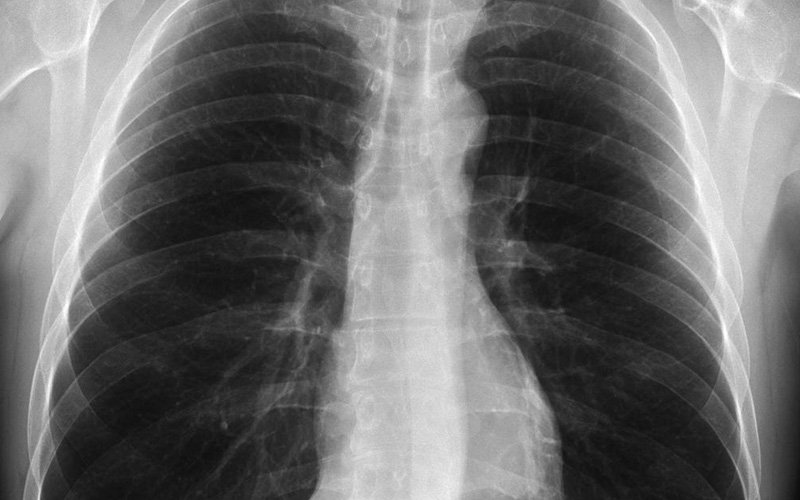

X-RAY

A chest X-ray can help in determining whether the heart is enlarged, which can indicate certain types of heart valve disease and other cardiac conditions.